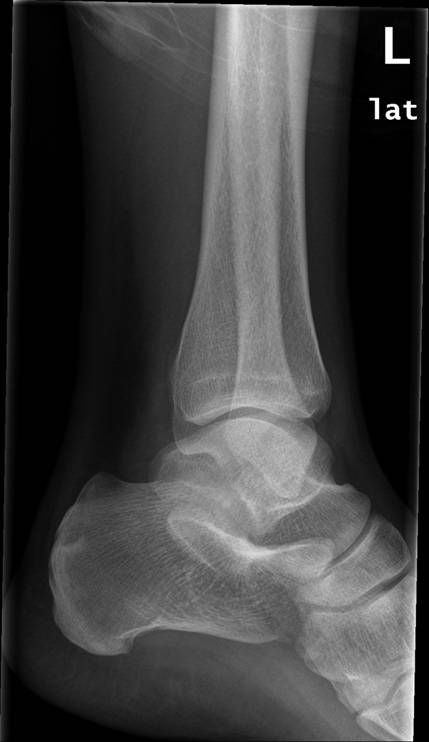

Fodled (2 projektioner), normal, røntgen

Normalt røntgenbillede af venstre fodled i 2 projektioner